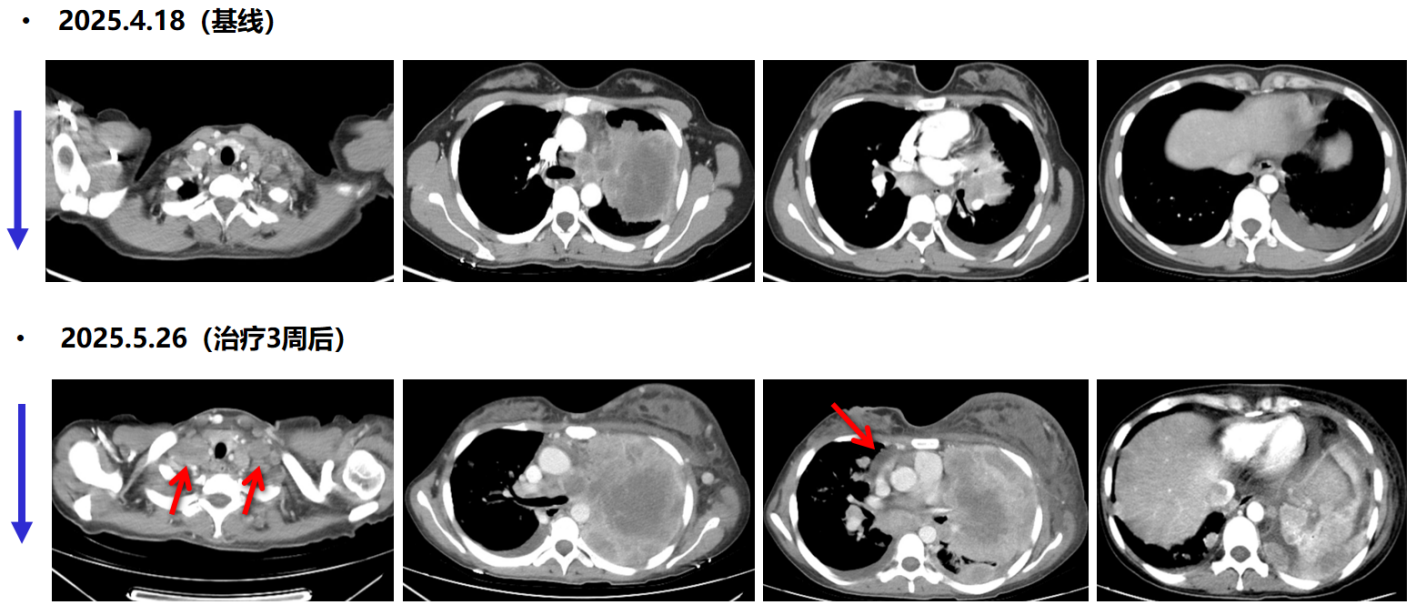

疗效评估:治疗仅3周后,患者病情迅速恶化。自觉胸闷加重,左乳及左侧肢体明显肿胀,胸部静脉怒张。2025年5月26日,胸部CT示左肺病灶及纵隔淋巴结较前明显增大,左乳皮下水肿明显,出现心包积液,2025年5月27日行心包穿刺引流黄色液体500ml。

111png.png

一线治疗前后胸部CT(纵隔窗)